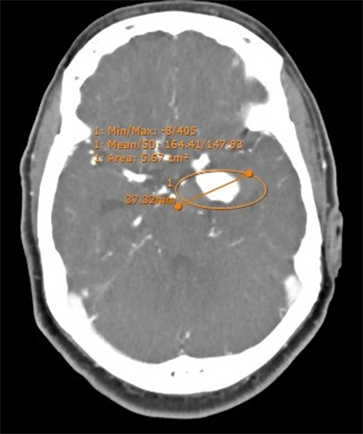

27.52% of aneurysm had small size, 42.20% had the medium size located ACA, MCA and Pcom, 20.18% large size against 5.50% of giant (Figure 3) and the middle cerebral artery was the most involved in the least.

Figure 3. CTA showing giant Pcom aneurysm partially thrombosed.